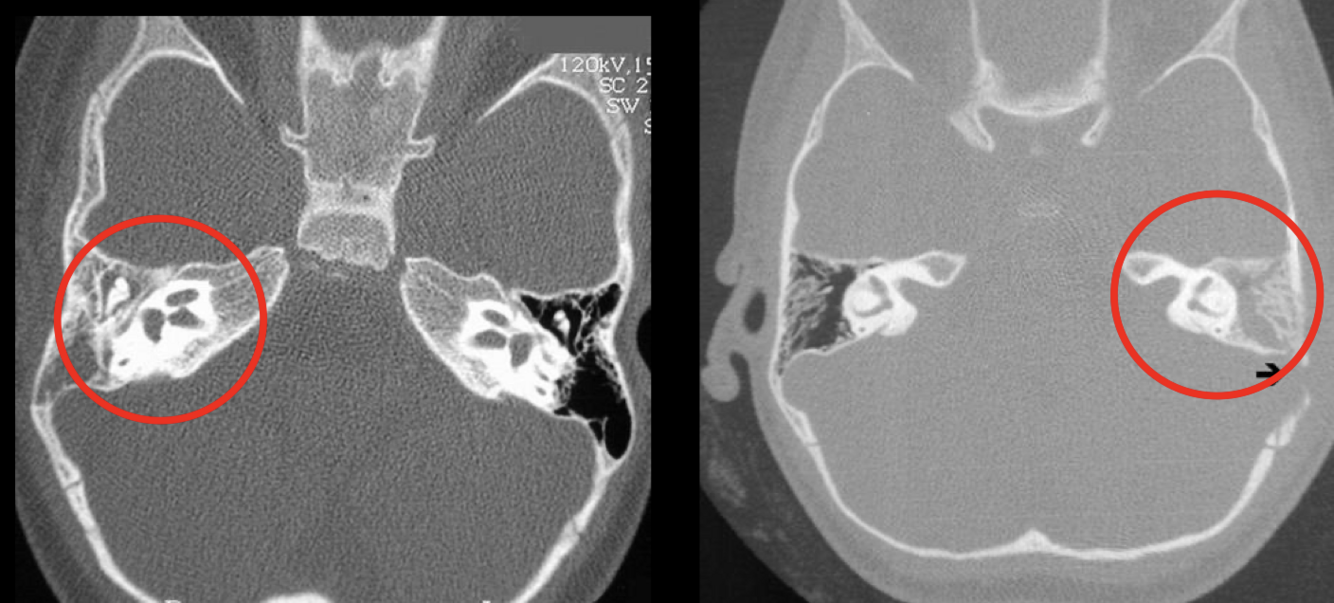

14

RM Colesteatoma